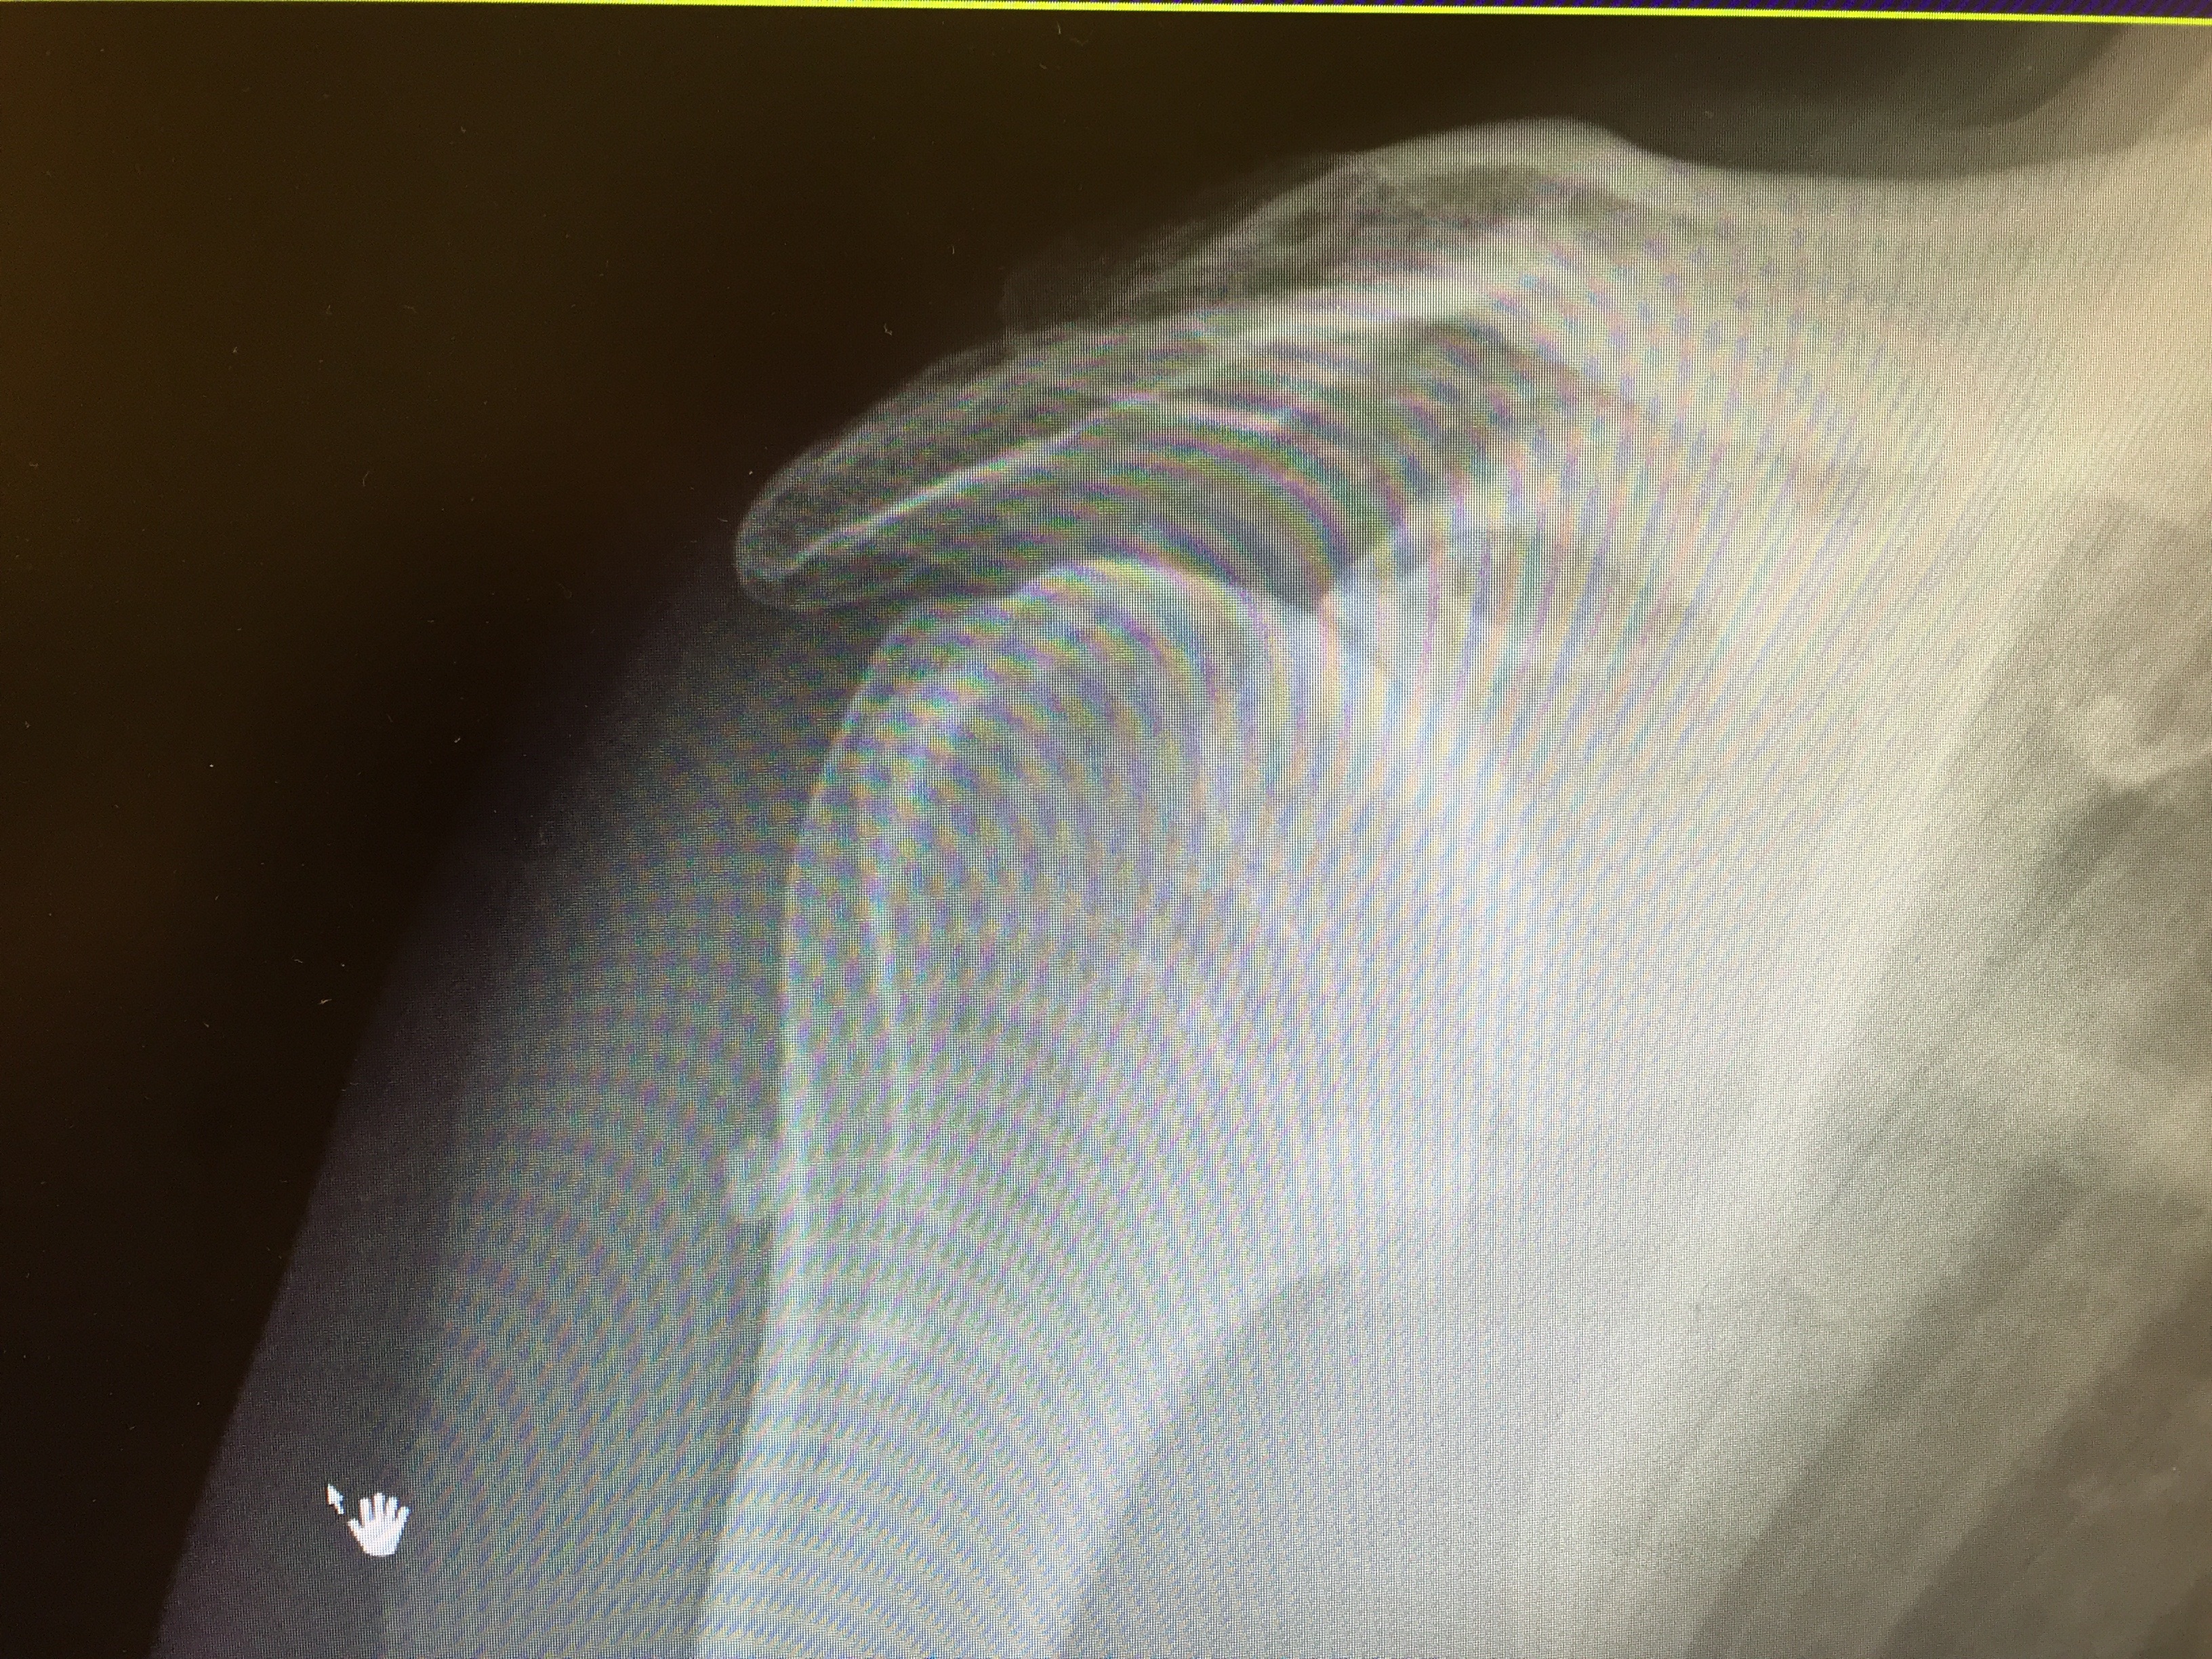

X Raying the Arthritic Shoulder What You Need to Know YouTube Arthritis On Shoulder Blade Symptoms of shoulder arthritis may include pain in the shoulder joint, stiffness and reduced range of motion. This is where the top of the. Arthritis can affect either of the joints in your shoulder. Five major types of arthritis typically affect the shoulder. There are five types of arthritis that can affect your shoulder, including rheumatoid arthritis and osteoarthritis. The. Arthritis On Shoulder Blade.

Shoulder Xray Century City Los Angeles, CA Commons Clinic Arthritis On Shoulder Blade Five major types of arthritis typically affect the shoulder. This is where the top of the. The glenohumeral joint is the larger of the two; There are five types of arthritis that can affect your shoulder, including rheumatoid arthritis and osteoarthritis. Your risk of developing osteoarthritis of the shoulder with its pain and physical limitations increases with age. Arthritis can. Arthritis On Shoulder Blade.